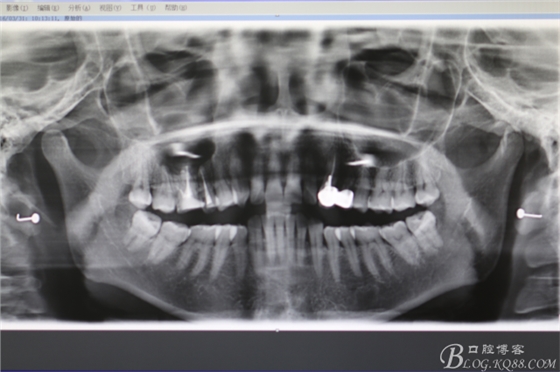

圖20.術(shù)后全景片影像檢查

圖21.局部放大影像:16腭根做根尖切除,近頰根行MTA倒充填